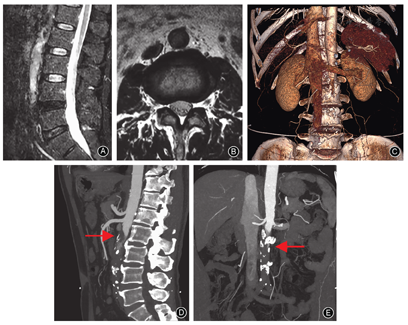

再次详细阅片,MRI未见明显腰椎间盘突出及腰椎椎管狭窄,但腰椎矢状位MRI T2WI(图1A)及轴位MRI T2WI(图1B)示腹主动脉管壁厚、毛糙,L2椎体水平以下腹主动脉腔内信号强度不均匀性增加,因此建议患者行腹主动脉CT血管造影检查。腹主动脉CT血管造影示腹主动脉及髂总动脉走行僵直,管壁不规则增厚,可见多发高密度钙化;双侧肾动脉开口水平以下腹主动脉及髂总动脉管腔增宽,部分层面管腔内见少许对比剂散在分布,余管腔未见明显对比剂充盈(图1C,图1D,图1E)。CT血管造影结论为腹主动脉及髂总动脉硬化并肾动脉开口水平以下腹主动脉及髂总动脉管腔重度狭窄及闭塞。最终诊断为Leriche综合征。再次就诊于血管外科,建议患者行主髂动脉人工血管转流术。该患者因医疗费用问题选择回当地医院治疗,但在术中因大量失血而死亡。